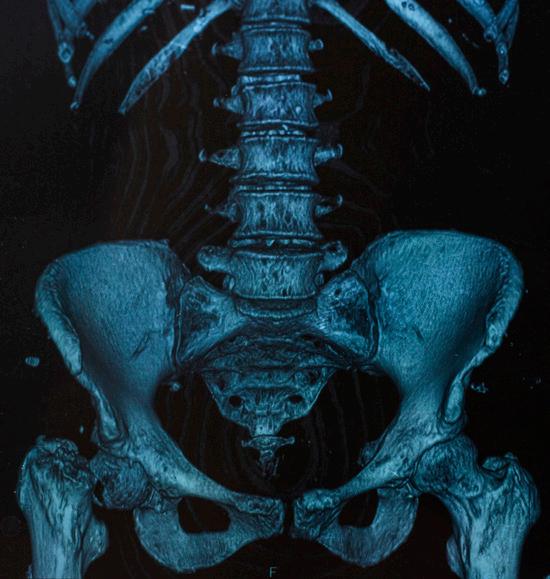

CT or CAT scan

Figure 12. X-ray of a hip fracture due to multiple myeloma

Computed tomography (CT), also called computed axial tomography (CAT), is a radiological study that uses X-ray technology to create a crosssectional, three-dimensional image of the inside of the body. It is a more precise study than X-ray and can provide clear, detailed images of bone.

¡ CT allows for the detection of small bone lesions that are not detectable by plain X-rays. In 20%–25% of patients with negative X-ray studies, whole-body CT will detect destructive bone lesions.

¡ CT can detect soft tissue masses that are not visible on X-ray.

¡ CT provides a more comprehensive assessment of fracture risk and the stability of collapsed vertebrae than X-ray.

To detect and document early bone disease, the IMWG recommends the use of whole-body low-dose CT (WBLDCT) as the preferred baseline imaging study for newly diagnosed myeloma patients. It has the following advantages:

¡ WBLDCT is faster and more convenient than WBXR.

¡ WBLDCT uses two to three times less radiation than conventional CT.

¡ WBLDCT does not require the use of contrast agents.

In 2017, the IMWG published a study, concluding that whole-body CT, either alone or as part of a PET-CT protocol, should be considered the current standard for the detection of osteolytic lesions in myeloma.

In 2018, the IMWG published its recommendations for acquisition, interpretation, and reporting of WBLDCT in patients with myeloma and other plasma cell disorders, thus establishing international protocol standards for this imaging study that can be followed by radiologists everywhere.

In 2019, the IMWG published guidelines on optimal use of imaging methods at different disease stages.

Despite its advantages, limitations of CT include:

¡ Like MRI, CT cannot be used for treatment monitoring because bone lesions in myeloma regress slowly or not at all, even in patients in complete remission.

¡ CT is not as sensitive as MRI in detecting lesions outside the bone marrow (extramedullary disease) or in the vertebrae and pelvis.

¡ CT is an expensive study.

¡ Even in low-dose format, CT uses an increased level of radiation as compared to X-ray or to MRI, which doesn’t use radiation at all.